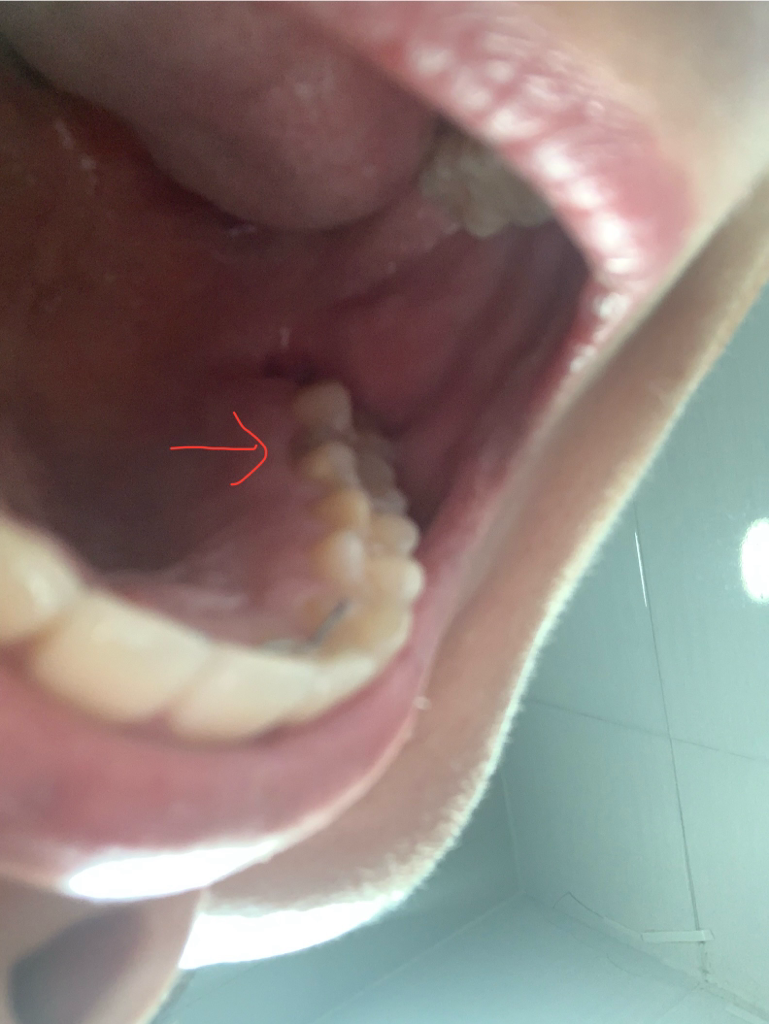

1. 첫번째 사진에서 빨간 화살표 있는 부분이 푸르스름 한데 이 부분 충치로 보이시나요?

충치일 가능성이 있어보입니다. 보다 정확한 확인을 위해 치과진료를 받길 권합니다.

2. 두번 째 사진은 사랑니 발치 후 1년이 지났습니다. 통증나 출혈은 없는데요

거울로 봤을 때 아직까지 사진에서 처럼 빈 공간이 보입니다.

정상인가요? 아니면 발치를 잘 못한건가요?

잇몸이 채워지는데는 개인마다 차이가 있으며 발치가 잘못된것은 아닙니다.